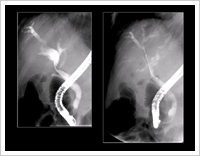

自己免疫性膵炎は膵臓外の種々の臓器にも病変が認められる全身疾患として注目されるようになり患者数が増加しています。CT、MR、ERCPをはじめガリウムシンチ、PETなども用いて全身を隈なく検査した後、ステロイドを用いて治療しています。

若手医師に対する教育では当科は日本消化器病学会、日本糖尿病学会の認定施設であり、学会の研修プログラムに沿い、専門医・指導医が取得できるよう教育を行っています。教育面では膵疾患の検査では上級医が知識と技量に問題ないと判断した者については、上級医の指導、監督の下、内視鏡的逆行性膵管胆管造影、超音波内視鏡検査、膵嚢胞に対する内視鏡的ドレナージ術等を行ってもらっています。